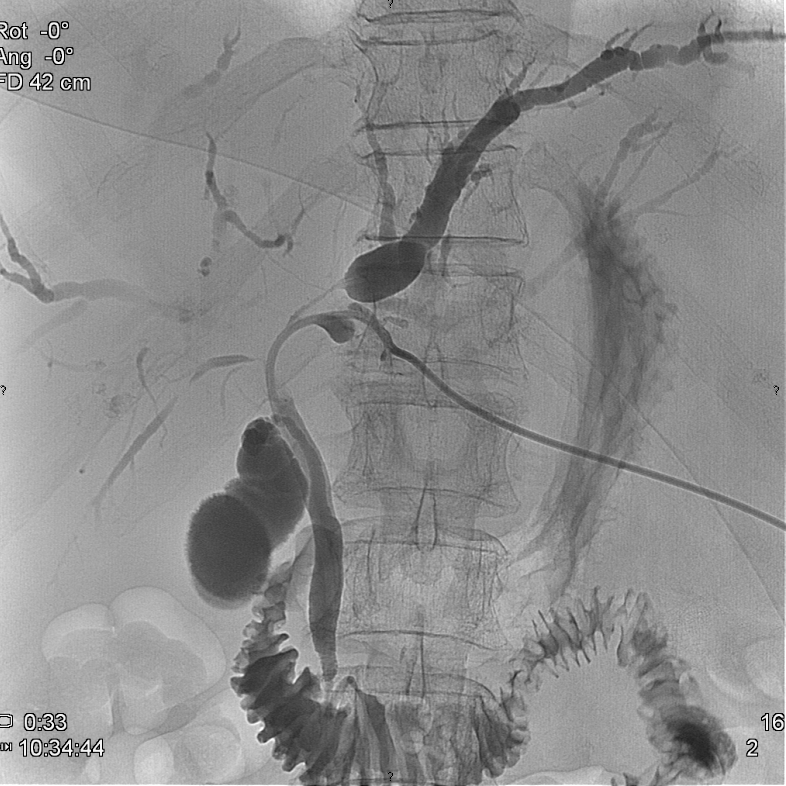

The most commonly performed intervention is US guided percutaneous nephrostomy. In special cases (obesity, visualization difficulties with US) CT guidance can also be chosen to create percutaneous nephrostomy. (Figure 30.)

Image

Figure 30. – Percutaneous nephrostomy contrast X-ray examination (CT guided catheter insertion)

In case the insertion of the catheter is not possible through the bladder in a retrograde manner, then the benign or malignant stenosis can be both overcome by inserting a hydrophilic – so called double J catheter – percutaneously.